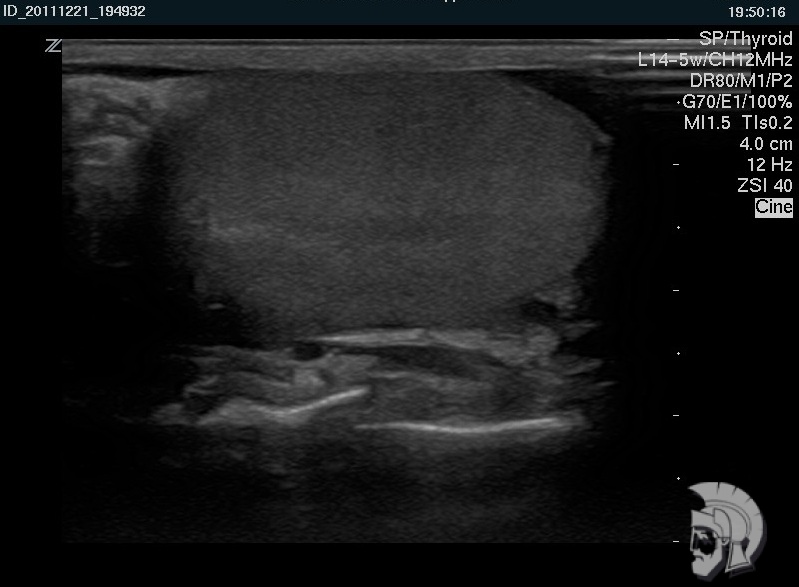

Фото УЗИ мошонки. Нормальная эхо-структура яичка мужчины 42 лет |

Фото УЗИ мошонки. Нормальная эхо-структура яичка мужчины 22 лет |